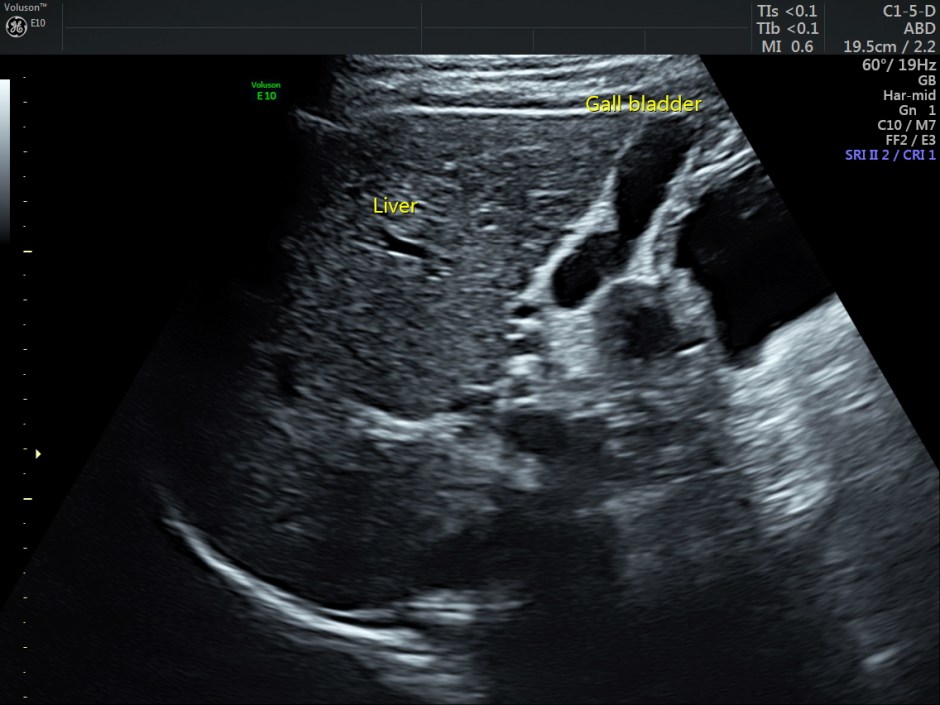

This was a 32-year-old woman, who was being evaluated for right upper quadrant pain.

Gall bladder appeared to be normal

Pancreas also appeared to be normal